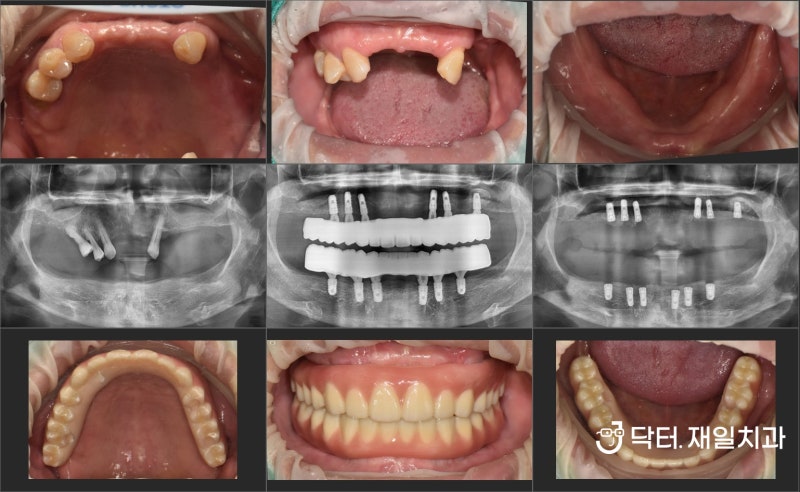

을 주소로 내원하신 20대 여성분인데 환자분의 오른쪽 어금니 교합은 아래 송곳니가 살짝 튀어나온 부분을 제외하면 어느 정도 괜찮을 것 같습니다.그런데 반대쪽 어금니를 보면 윗니에 가려져 아랫니가 거의 보이지 않는 상태에서 아랫니 어금니가 혀 쪽으로 넘어지면서 윗니 아랫니가 전혀 맞물리지 않는 상태입니다.가위교합(scissors bite)이라고 하는데 윗니는 뺨 쪽으로, 아랫니는 혀 쪽으로 완전히 엇갈린 교합의 양상이며, 이 교합은 시간이 지남에 따라 점점 심각해집니다.따라서 오랜 시간이 지나면 상하 어금니 치주(치경)가 나빠지고 어금니 전체를 발치하는 경우도 흔합니다.또한 정면 사진에서 위쪽 화살표를 보면 좋지 않은 교합 때문에 잇몸 마모증(Cervical abfraction)도 있습니다.

윗니 어금니가 뺨 쪽으로 많이 어긋난 상태입니다.치아가 조금씩 구부러져 있는 부분은 가위의 교합 교정을 하는 과정에서 자연스럽게 정돈된다고 생각됩니다.(교정치료를 치아를 다듬는 것으로만 생각할 수 있지만, 삐끗한 부분이 정돈되는 과정이 가장 쉽고 빠르게 중요한 것은 상하교합을 기능적으로 정상화하는 것입니다.)) 직업상의 이유로 장치를 부착할 수 없어 제거해야 하는 기간이 일시적으로 있었음에도 약 1년 정도의 기간으로 가짜 교합을 정상 교합에 맞추면서 치료를 종결하였습니다.

완전히 엇갈리고, 그 엇갈림으로 윗니가 많이 내려왔던 것도 해소되었습니다.완전히 엇갈리고, 그 엇갈림으로 윗니가 많이 내려왔던 것도 해소되었습니다.가위교합교정을 하게 되면 그동안 씹지 않았던 부분이 상하교합이 잘 되어 처음에는 어색함과 불편함이 있을 수 있는데, 이는 시간이 지나면서 서서히 적응하게 됩니다.위아래로 어긋나던 중심선도 잘 맞아떨어졌습니다.교정이 필요하거나 씹는 데 불편을 느끼신다면 치과의원에 가셔서 정확한 진단을 받아 보시기 바랍니다.이상 오늘 포스팅을 마치겠습니다.감사합니다。더바른치과병원 서울특별시 송파구 석촌호수로 61 트리지움상가 201호 더바른치과병원더바른치과병원 서울특별시 송파구 석촌호수로 61 트리지움상가 201호 더바른치과병원더바른치과병원 서울특별시 송파구 석촌호수로 61 트리지움상가 201호 더바른치과병원